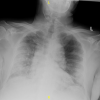

Figure 1

Chest X-ray showing COVID-19 pneumonia during initial presentation to the hospital. The X-ray shows hazy parenchymal opacities in the right mid and lower lung as well as the left lower lobe. Reticular opacities are seen in the medial right lower lobe. There is a concern for widening of the mediastinum, although likely projectional. A CT scan is needed to rule out any mediastinal pathology.